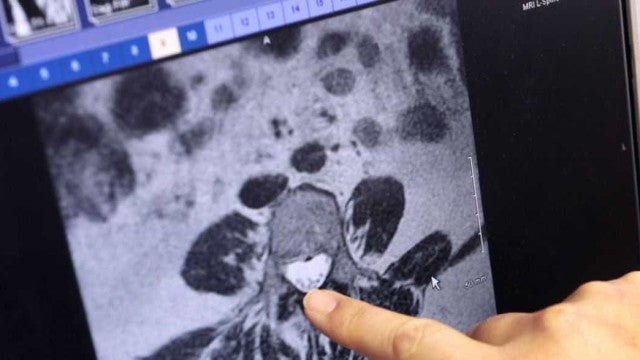

O câncer de tireoide afeta três vezes mais mulheres do que homens, sendo a quinta principal causa de câncer do tipo não melanoma neste grupo, com uma incidência estimada de 14 mil novos casos no triênio 2023 a 2025.

De acordo com estimativas do Inca (Instituto Nacional do Câncer), a estimativa é que sejam registrados 49,8 mil novos casos de câncer de tireoide nos próximos três anos. O risco aproximado é de 7,68 casos a cada 100 mil habitantes, mas a taxa pode variar de acordo com a região do país. No Sudeste, é o terceiro tipo de câncer mais frequente (16,53 por 100 mil).

O principal tratamento indicado para o câncer de tireoide é a cirurgia, a iodoterapia e a terapia hormonal. Raramente existe a indicação de radio ou quimioterapia. Nos pacientes em que a cirurgia ou a radioterapia não funcionaram, há a indicação do uso de terapia-alvo.